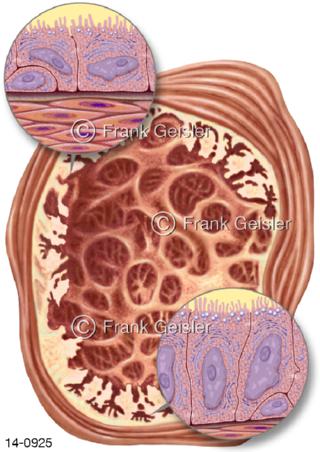

Bildergalerie Urogenitalsystem

Bilder zum Urogenitalsystem mit Urogenitalorgane, Urogenitaltrakt, zum Harn- und Geschlechtsapparat, Harnorgane und Geschlechtsorgane, Organe der Harnwege und der Fortpflanzung, Harnorgane und Geschlechtsorgane im männlichen und weiblichen Urogenitalsystem